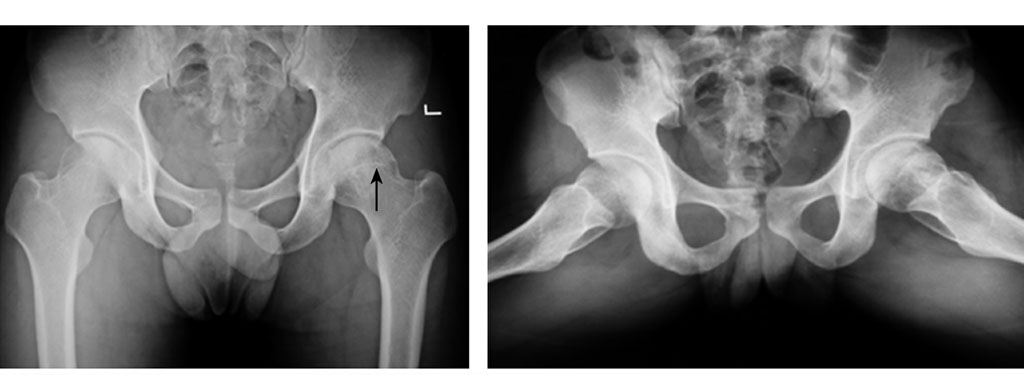

(二)X线检查

X线摄片可显示Ⅱ期骨坏死,股骨头内硬化(↑)

诊断早期(0,Ⅰ期)骨坏死是不可能的,Ⅱ期以上的部分病灶可呈阳性改变,如硬化带、透X线的囊性变,斑点状硬化等,Ⅲ期骨坏死可较清楚显示。推荐双髋后前位(正位)和蛙式位。